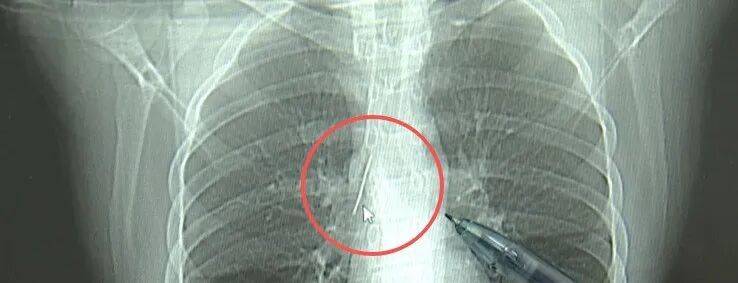

近日,安徽17岁小伙小陆参加征兵体检,胸片结果显示:胸腔内有一处金属高密度影,形态细长,像一根针。

进一步的CT检查确认,异物是一枚金属针,斜插在肺组织内,位置十分凶险。

杭州市第一人民医院心胸外科副主任 冯兴:“我们看到这个针的尖锐部,正好指向他体内的一个大血管,边上是上腔静脉和胸主动脉,因此这个针稍有不慎,就有可能造成周边血管的损伤,甚至危及生命。”